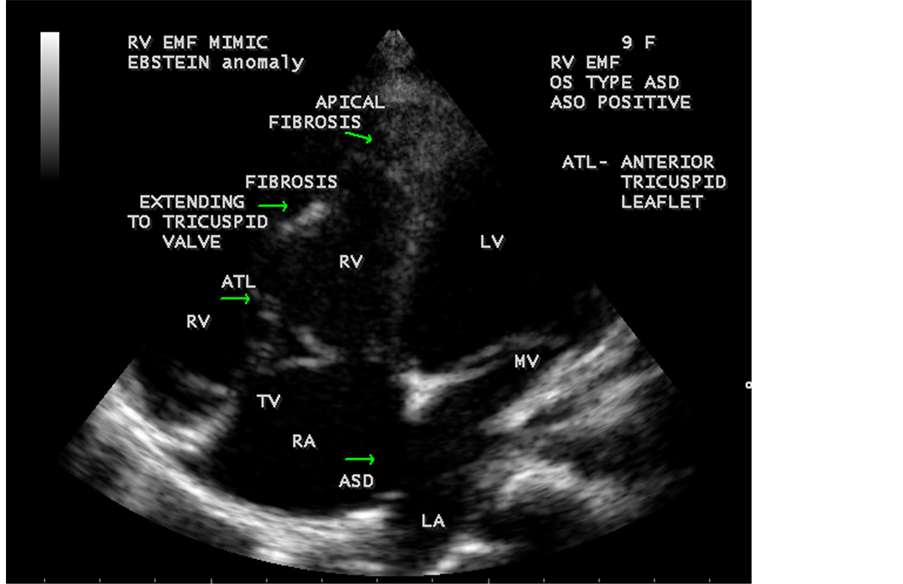

Figure 64. RV EMF associated with ostium secundum atrial septal defect with rheumatic mitral valve involvement in a 9-year-old female with positive serum ASO titer (anti-streptolysin O).

Figure 65. RV EMF with ASD (atrial septal defect) in a 9-year-old female.

Figure 66. RV EMF with ASD-mimic Ebstein’s anomaly in a 9-year-old female (apical fibrosis extending to tricuspid valve and the valve is tethered with fibrosis and mimic Ebstein’s malformation of the tricuspid valve and the right ventricle (RV) is dilated due to left to right shunt).